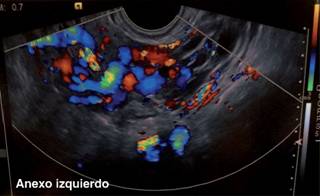

El ultrasonido Doppler transvaginal mostró presencia de venas ováricas mayores a seis milímetros, con aumento de velocidades y flujo reverso de manera bilateral (Figura 1).

Figura 1: Ultrasonido Doppler transvaginal con presencia de venas ováricas mayores a 6 mm, con aumento de velocidades y flujo reverso de manera bilateral.